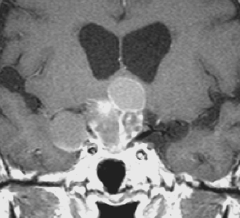

成人の第3脳室内部に局在する頭蓋咽頭腫です。経脳梁法で両側のモンロー孔から全摘出しました。下垂体組織は残っています。これは乳頭状頭蓋咽頭腫と呼ばれるもので,成人にしか発生しません,のう胞がなく石灰化もないのが大きな特徴です。境界が明瞭で柔らかく摘出が簡単なタイプとして知られています。この患者さんも術後に下垂体機能不全も視床下部障害も生じませんでした。